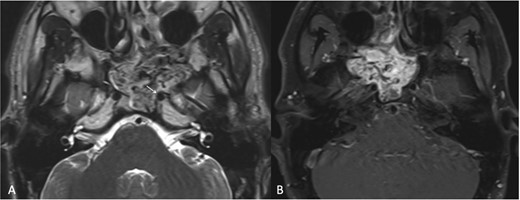

A 9-year-old previously healthy male was referred due to left nasal blockage and mild intermittent epistaxis persisting for 6 months. Nasal endoscopy revealed a clearly evident pinkish mass in the left nasal cavity. Non-contrast Computed Tomography (CT) of the paranasal sinuses (Fig. 1a and b) demonstrated a large, expansile, and ill-defined soft tissue mass with its epicenter in the left nasal cavity and nasopharynx. It extends to the left pterygopalatine fossa and the pterygomaxillary fissure, reaching the masticator space. The mass caused significant bone remodeling and expansion, with some erosions noted at the body and the left greater wing of the sphenoid bone, as well as the medial and lateral pterygoid plates. Additionally, the mass was seen extending to the lateral walls of the maxillary and ethmoid sinuses, bilateral sphenoid sinuses, and the inferior bony orbital wall. Contrast-enhanced Magnetic Resonance Imaging (MRI) showed a predominantly left-sided nasopharyngeal mass measuring 6.9 × 5.9 × 5 cm with increased vascularity (Fig. 1c). The mass replaced the left maxillary antrum, posterior ethmoid air cells, and sphenoid sinuses and invaded the left cavernous sinus (Fig. 1d). A pre-operative left ICA angiogram demonstrated the tumor’s blood supply originating from the vidian artery and inferolateral trunk, with the main supply arising from branches of the left internal maxillary artery (IMA). The vascular branches feeding the tumor from both IMAs were embolized.

(a) Axial non-contrast CT of the paranasal sinuses showing a soft tissue mass obliterating the posterior aspect of the nasal cavity, with extension and remodeling of the left pterygopalatine fossa into the infratemporal fossa. (b) Coronal image demonstrating superior extension into the left sphenoid sinus and left inferior orbital fissure. (c) Coronal T2-weighted MRI showing a large JNA with heterogeneous signal intensity and multiple flow voids consistent with hypervascularity. (d) Post-contrast coronal T1-weighted MRI demonstrating avid contrast enhancement and invasion of the left Meckel’s cave and cavernous sinus (arrow).